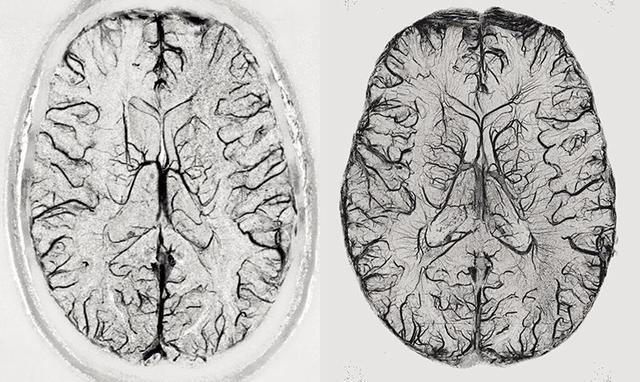

圖 | 使用3T(左)和9.4T(右)核磁共振掃描儀的大腦成像對比(來源:Rolf Pohmann/Max-Planck-Institute for Biological Cybernetics)

7T 及更強(qiáng)的核磁共振掃描儀在進(jìn)行腦成像時(shí),分辨率可達(dá)到 0.5 毫米以下,這足以分辨人體大腦皮質(zhì)區(qū)里的功能單位,甚至可以讓我們有機(jī)會(huì)了解活體大腦神經(jīng)元細(xì)胞之間的信息流動(dòng)情況,為非侵入的精準(zhǔn)醫(yī)學(xué)奠定了基礎(chǔ)。關(guān)于磁共振成像的發(fā)現(xiàn)也于 2003 年獲得諾貝爾生理學(xué)或醫(yī)學(xué)獎(jiǎng)。